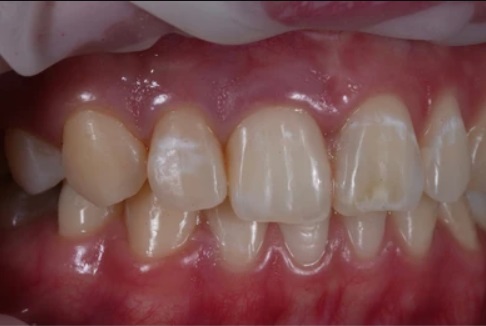

The symptoms and signs of dental fluorosis can vary depending on the severity of the condition. In mild cases, there may be barely noticeable white streaks or spots on the enamel. However, as the severity increases, the appearance of the teeth can be significantly affected.

Moderate to severe fluorosis can lead to brown stains, pitting, or cracking of the enamel, making the teeth more susceptible to tooth decay and sensitivity. It is important to be aware of these symptoms and consult with a dental professional for an accurate diagnosis and appropriate treatment.